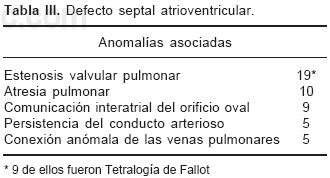

La anatomía básica de los 2 tipos de DSA–V fue la misma. Todos presentaron anillo fibroso A–V común, reducción de la distancia A–V–ápex e incremento de la distancia ápex –válvula aórtica, el tabique ventricular estuvo excavado (Figs. 4 y 6C), el anillo fibroso mostró dilatación anteroposterior, desencuñamiento aórtico, alteración en el esqueleto fibroso del corazón consistente en un anillo fibroso A–V común, ausencia del septum membranoso y persistencia de la continuidad entre la válvula aórtica y la válvula A–V común o válvula A–V izquierda (Fig. 6D), desviación anterior del tracto de salida del ventrículo izquierdo (Figs. 4 y 6C) y en dos especímenes obstrucción de éste por inserción en su interior de la valva anterosuperior izquierda (Fig. 7A). En un espécimen con una válvula A–V común se desarrolló una banda anómala de miocardio entre la pared libre y el tabique ventricular, lo que separó el componente derecho de la válvula A–V común en dos orificios valvulares (Fig. 7B). Las alteraciones asociadas se consignan en la Tabla III.